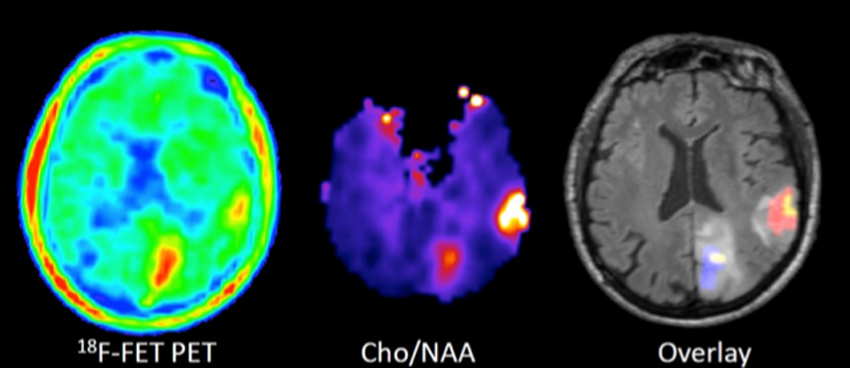

Die Arbeitsgruppe befasst sich mit der präklinischen und klinischen Bewertung neuer Radiopharmaka für die Diagnostik von Hirntumoren mit der Positronen-Emissions-Tomographie (PET) und der korrelativen Bildgebung mit der Magnet-Resonanz-Tomographie (MRT).

Die Arbeiten konzentrieren sich auf die Evaluierung der intratumoralen Anreicherung von radioaktiv markierten Aminosäuren in Hirntumoren im Vergleich mit modernen Methoden der funktionellen MR-Bildgebung sowie die klinische Anwendung der korrelativen MR-PET Bildgebung in der Diagnostik, Therapieplanung und Therapiekontrolle bei Patienten mit Hirntumoren.